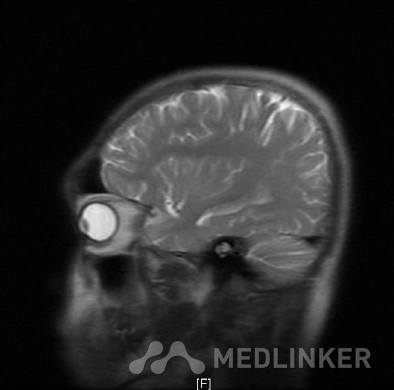

MR:双侧额叶及左侧颞叶异常信号,结合病史,多考虑脑挫裂伤(亚急性-慢性期);双侧下鼻甲肥厚。左侧蝶窦黏膜增厚。

诊断:1.多发脑挫裂伤2.蛛网膜下腔出血3.枕骨骨折 入院后积极予以预防癫 痛、预防脑血管痉挛、营养神经、护胃等对症支持治疗.